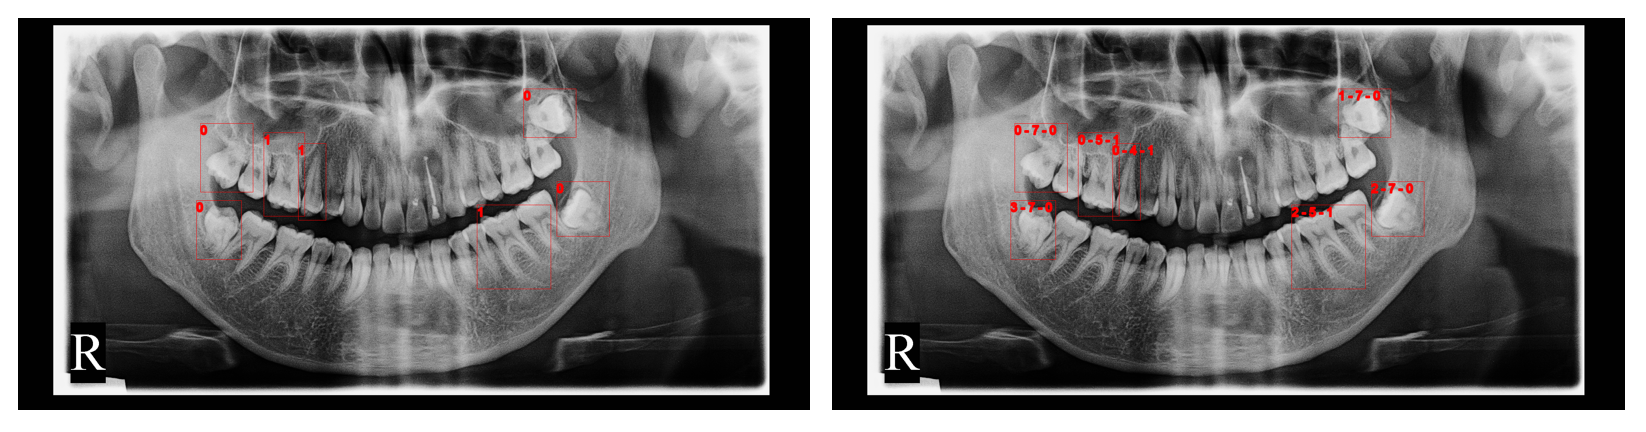

Quantitative results are shown in Fig. 2 3 4.

In Fig. 2, we show the origin image, teeth bounding boxes from the teeth detection model, and teeth segmentation masks from the teeth segmentation models, respectively. The bottom-left segmentation mask is from U-Net, and the bottom-right segmentation mask is from SE U-Net. We use eight colors to draw the masks while they are actually 32 classes.

Refer to caption

Figure 2: Origin image, detection and segmentation result on whole image